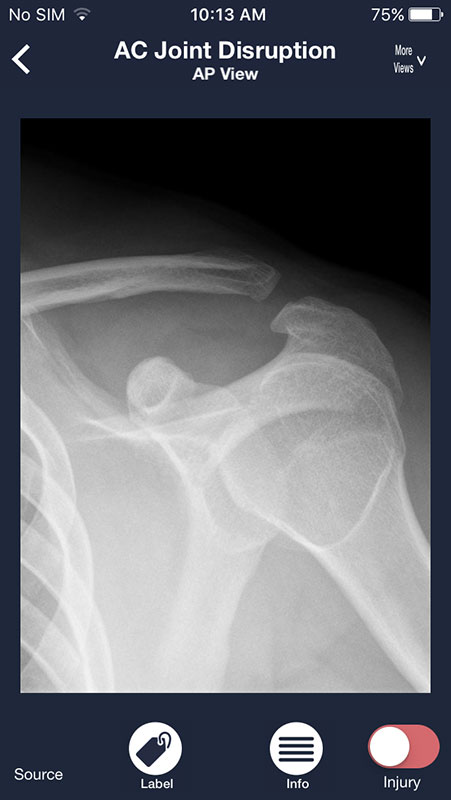

The other button, Injuries, features the list of most common injuries/pathologies related to a particular body part. For example, shoulder injuries such as AC joint disruption or proximal humerus fracture, or heart failure or pulmonary nodule in chest radiographs.

While in the Injury view, you can also select Label to view any abnormalities annotated, or Info button which provides users with the explanation of the presentation and X-ray findings, as well as management recommendations, without references used.